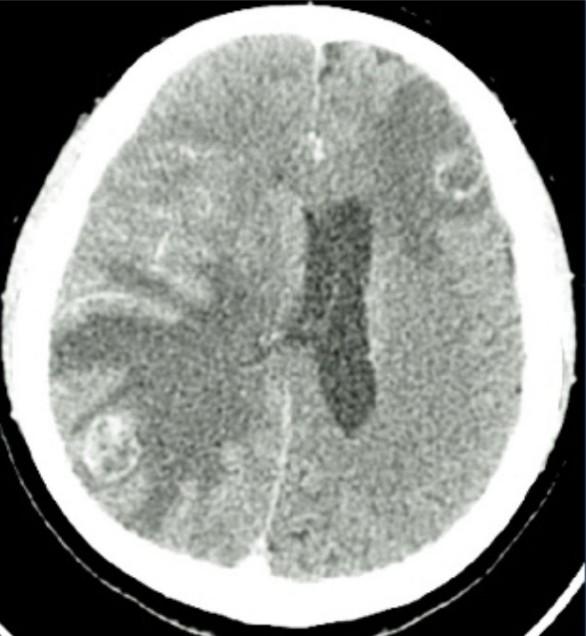

HIV patient with focal neurological deficit

A 45-year-old man with untreated HIV presents with fever, headache, confusion and right-sided weakness.